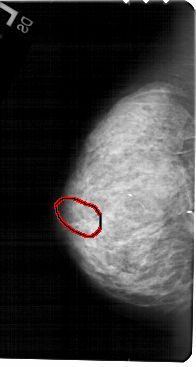

A_1325_1.LEFT_MLO

LEFT_MLO LINES 5476 PIXELS_PER_LINE 2761 BITS_PER_PIXEL 12 RESOLUTION 43.5 OVERLAY

FILE: A_1325_1.LEFT_MLO.OVERLAY

TOTAL_ABNORMALITIES 1

ABNORMALITY 1

LESION_TYPE CALCIFICATION TYPE PLEOMORPHIC DISTRIBUTION CLUSTERED

ASSESSMENT 4

SUBTLETY 2

PATHOLOGY BENIGN

TOTAL_OUTLINES 1

BOUNDARY